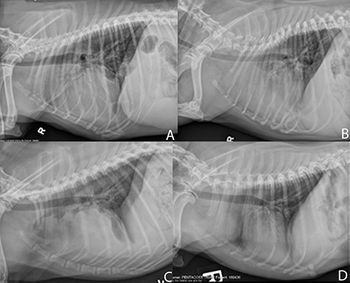

Dr. Adrien Hespel provides the radiology perspective on this thymoma case.